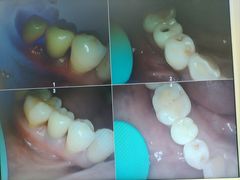

• 牙博士口腔品牌连锁(杨浦店)

• -牙博士口腔品牌连锁(杨浦店)